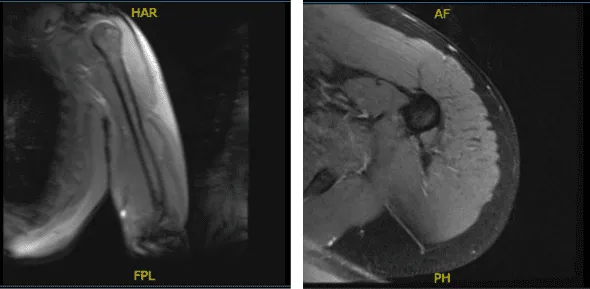

MRI results were presented and reviewed by the doctor. It showed that there is traction cyst in the greater tuberosity. There is a complete tear of the distal biceps’ tendon with tendon retraction to the level of the radial capitellum joint line with fluid along the course.

MRI-3T Left Arm Non-contrast